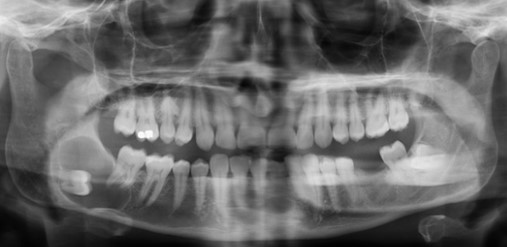

如果医生怀疑是颌骨囊肿,通常会建议患者拍摄X线片或做一次口腔CT。在片子上,囊肿会显示为一个边界清晰的“暗区”,和正常的骨头区分得很明显。

所以,定期做口腔检查非常重要。很多囊肿就是在体检拍片时偶然发现的,这时范围还小,处理起来也相对简单。